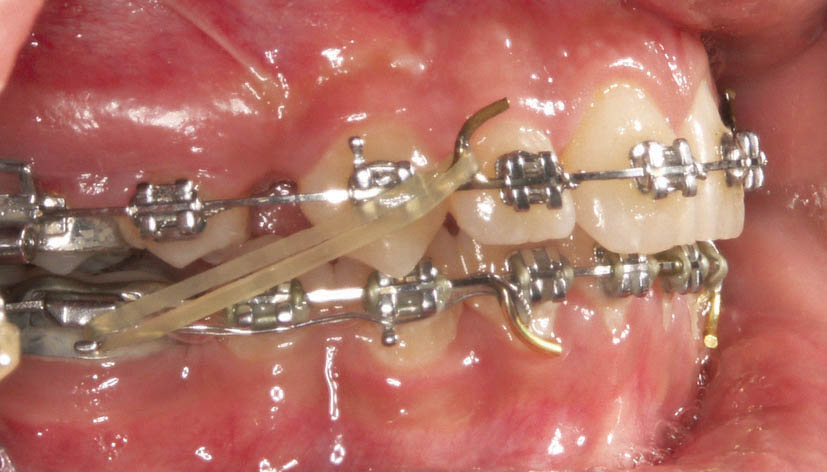

وقتی رابطه مولری کلاسIII است لاتکسها را از سگمنت خلف بالا به سگمنت قدام پایین میاندازید تا هم خلفیهای بالا جلو بیایند و رابطه مولری را اصلاح نمایند و هم قدام پایین عقب برود و اورجت را اصلاح نماید. به این نوع لاتکس اصطلاحاً الاستیک کلاسIII میگویند (شکل 40-4).

شکل 40-4: الاستیک کلاسIII